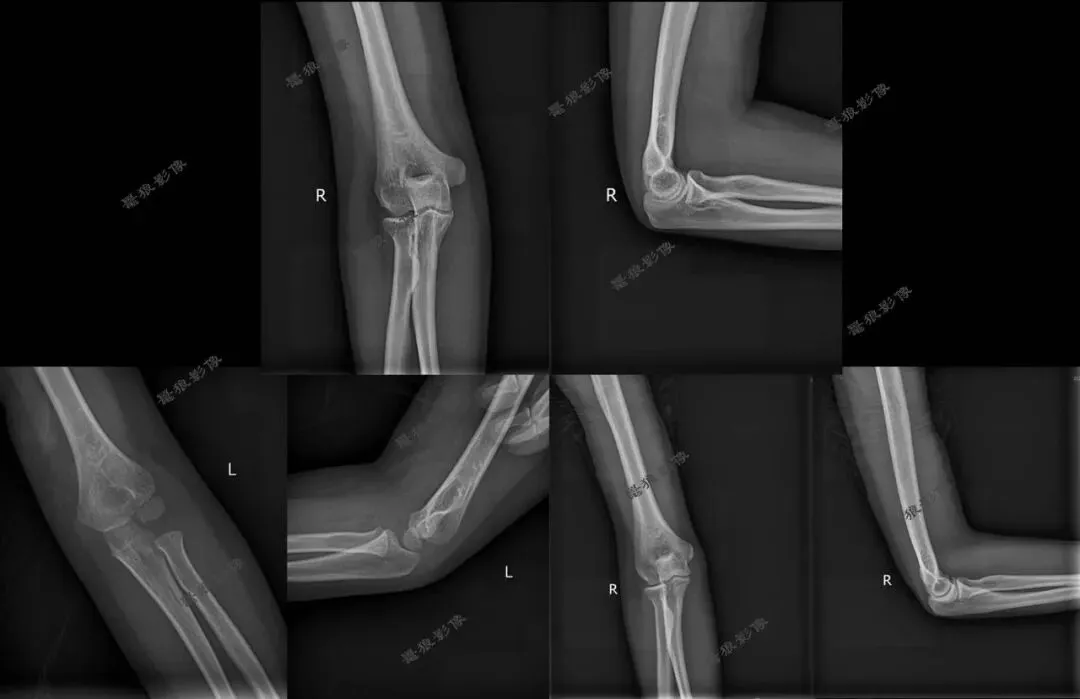

一、先来看几组图片

我们再看肘关节几组图片